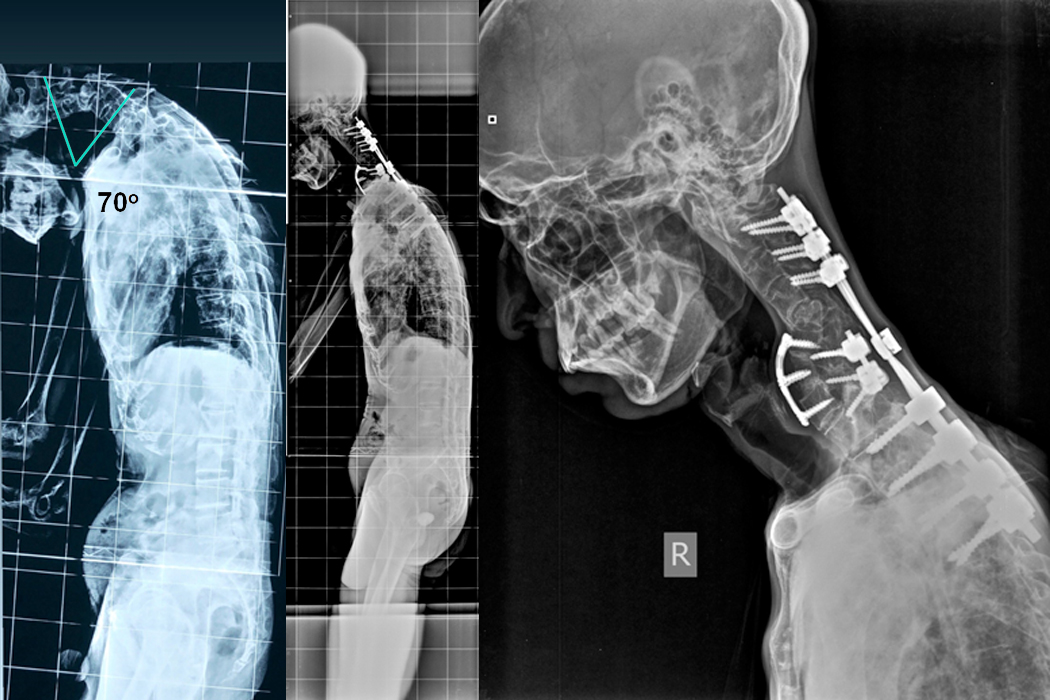

Patient D

A 46 year old male presented with progressive deformity of the neck (Chin-on-chest deformity) for last 6 months after lifting heavy weight on head, weakness of all 4 limbs with gait instability and urinary problems for which he was catheterised since 2 months. He was initially put on Halo gravity traction and then Combined Anterior and Posterior fixation with decompression and Deformity correction was done on 23.07.2019.